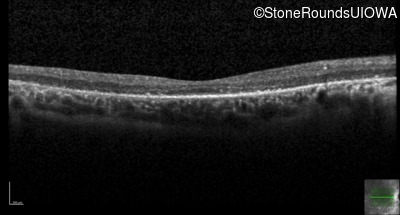

Optical Coherence Tomography - Left - 20/50 -1 sc

Exemplar / OCT Stack

OCT Stack